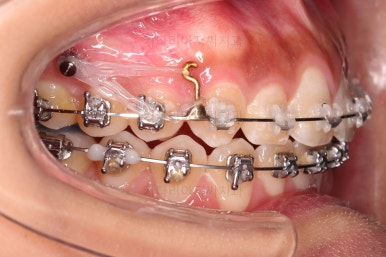

어쨌든 윗니는 뒤로 밀어줘야 교합이 맞아지기 때문에 미니스크류를 이용해서 약간이나마 뒤로 밀어주기로 했고 + 하는 김에 입매를 전체적으로 들어가게 하기로 했습니다.(처음보다 더 들어가게)

미니스크류를 식립을 하고요.

뒤로 뒤로 당겨줍니다.

만족하실 때까지 당겨줍니다.

교합도 신경 써주고요.